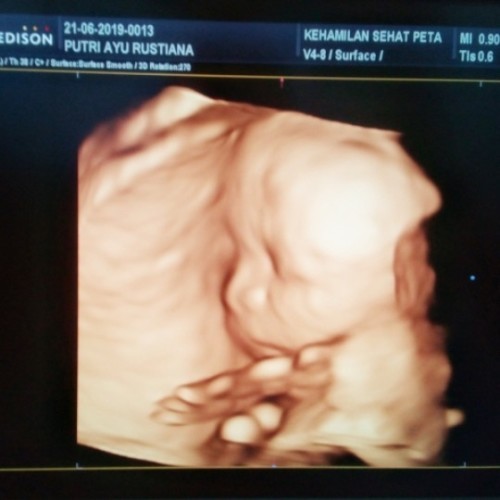

USG di 26 minggu

bun mau tanya kmarin aku usg di usia kehamilan 26 minggu tpi aku ga ngerti itu baca gambar usgnya gimna ya bun ? mohon pencerahannya .. oiya trus jg ktnya janinku kecil tapi dokternya ga nyebutin brpa gram kn jd bingung bun .. trus jg babynya sungsang apa di usia kehamilan sgtu masih bisa muter2 bun ?